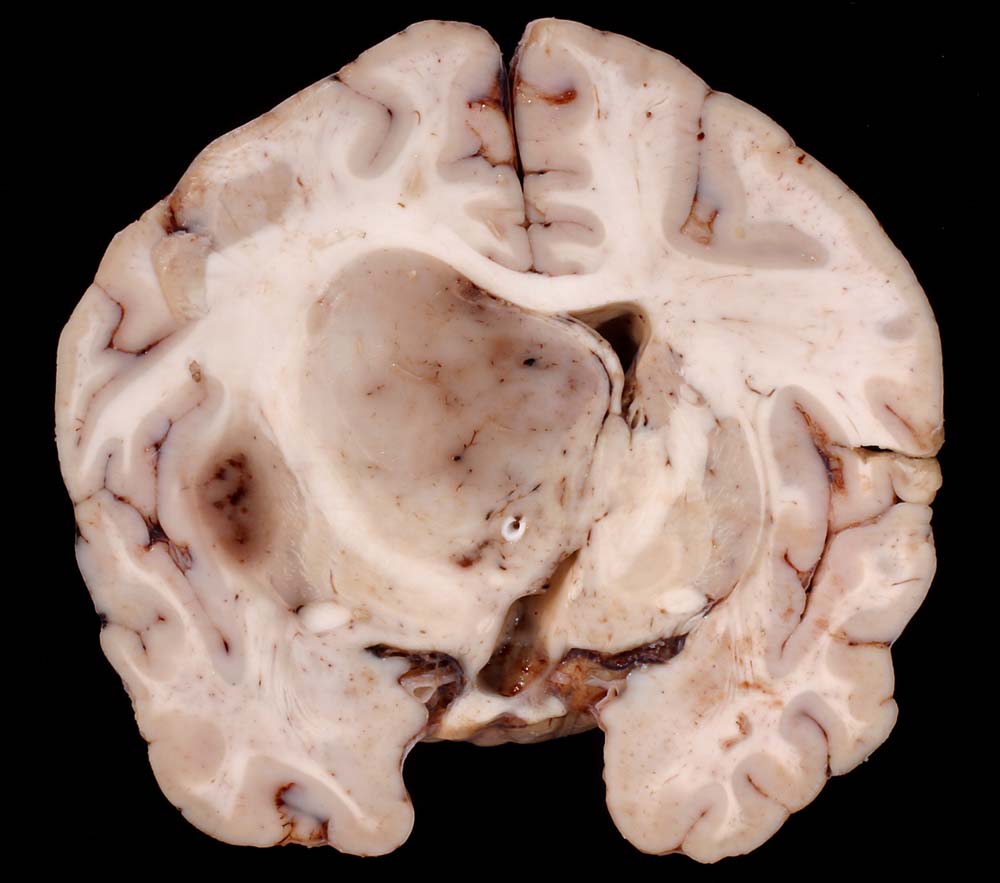

PathoPic ID 8766 - Anaplastisches Oligodendrogliom

Anaplastisches Oligodendrogliom

maligner Tumor

Hirn parietal

Nervensystem

Gräuliches Tumorgewebe verschiebt die Mittellinie stark zur Gegenseite und komprimiert den Seitenventrikel.

Anaplastisches Oligodendrogliom Grad III nach WHO.

Thalamus-Tumor. Hydrocephalus bei Tumoreinblutung. Einklemmung.

Makroskopie